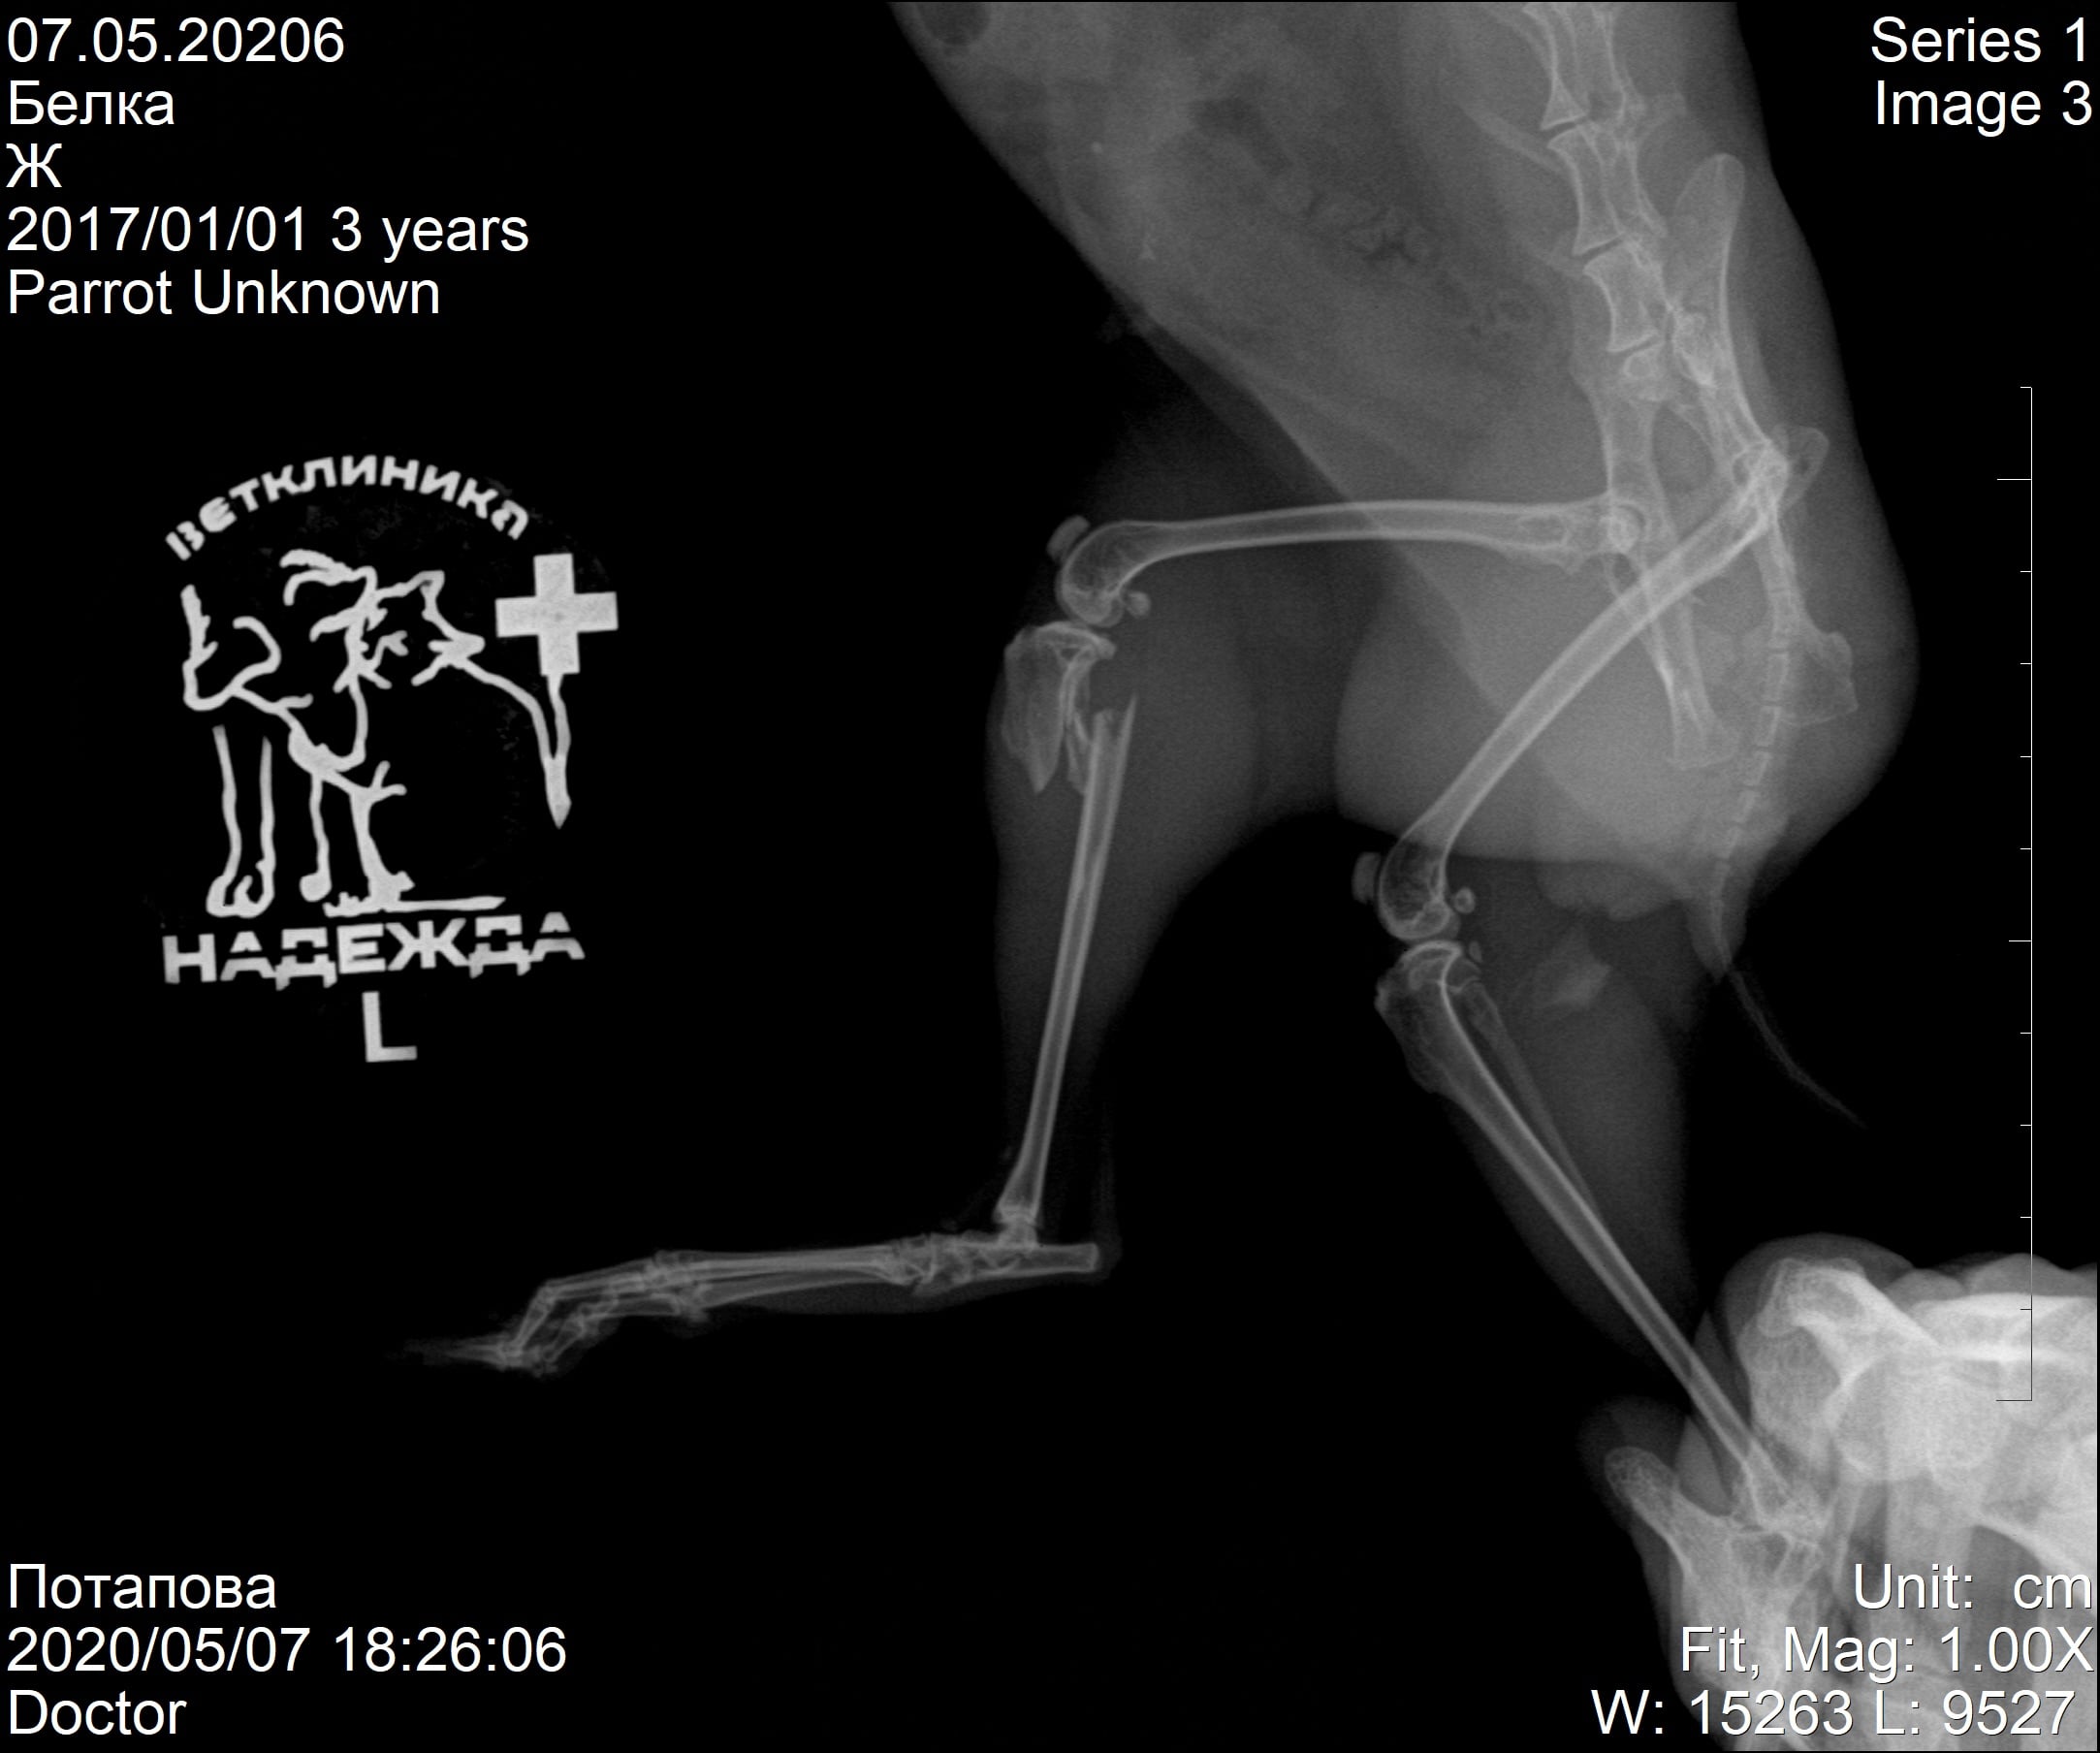

Случаи из практики

Ветеринарная клиника Надежда

За более чем 30-ти летнюю практику наши ветеринары сталкивались в различными случаями болезней и травм животных. Это дало нам огромный опыт в лечении и реабилитации. Мы беремся даже за самые сложные случаи! С любовью и заботой относимся к животным, стараемся сделать так, чтобы они испытывали минимум дискомфорта во время лечения и реабилитации.